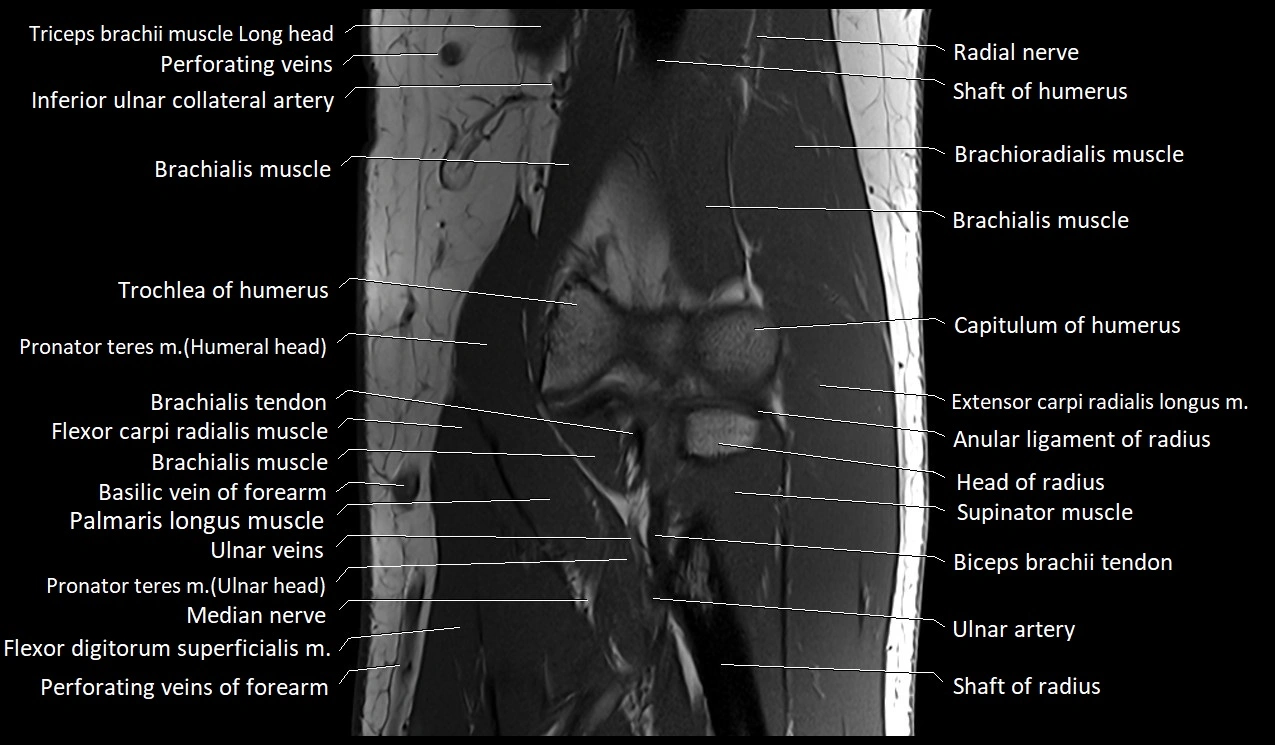

MRI image

image